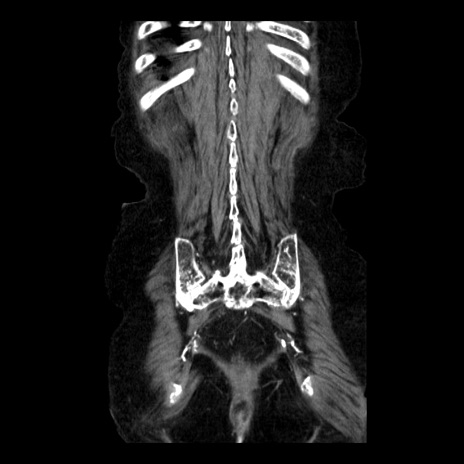

横断像

症例14(冠状断像)

【症例】 90歳代女性

【主訴】 腹痛・嘔吐

【現病歴】今朝から左側腹部痛を認めた。 経過観察していたが、嘔吐を認めたため来院。

【既往歴】 子宮癌術後

【身体所見】 意識清明、BP 127/54mmHg、P 98bpm Sp02 95%(RA)、BT 35.8°C、腹部平坦・軟腸ぜん動音聴取良好、右下腹部圧痛(+) 反跳痛なし

【データ】WBC 9800、CRP 0.46